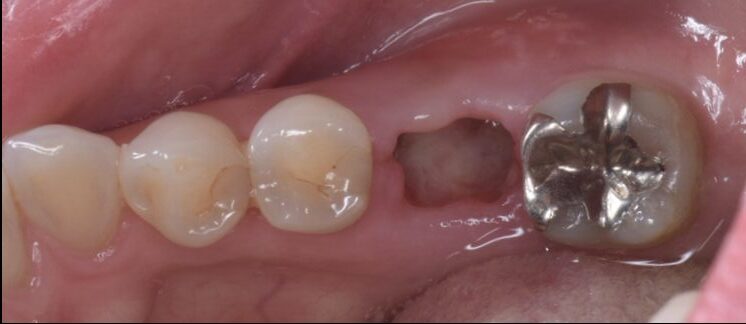

Before

抜歯後2週間後